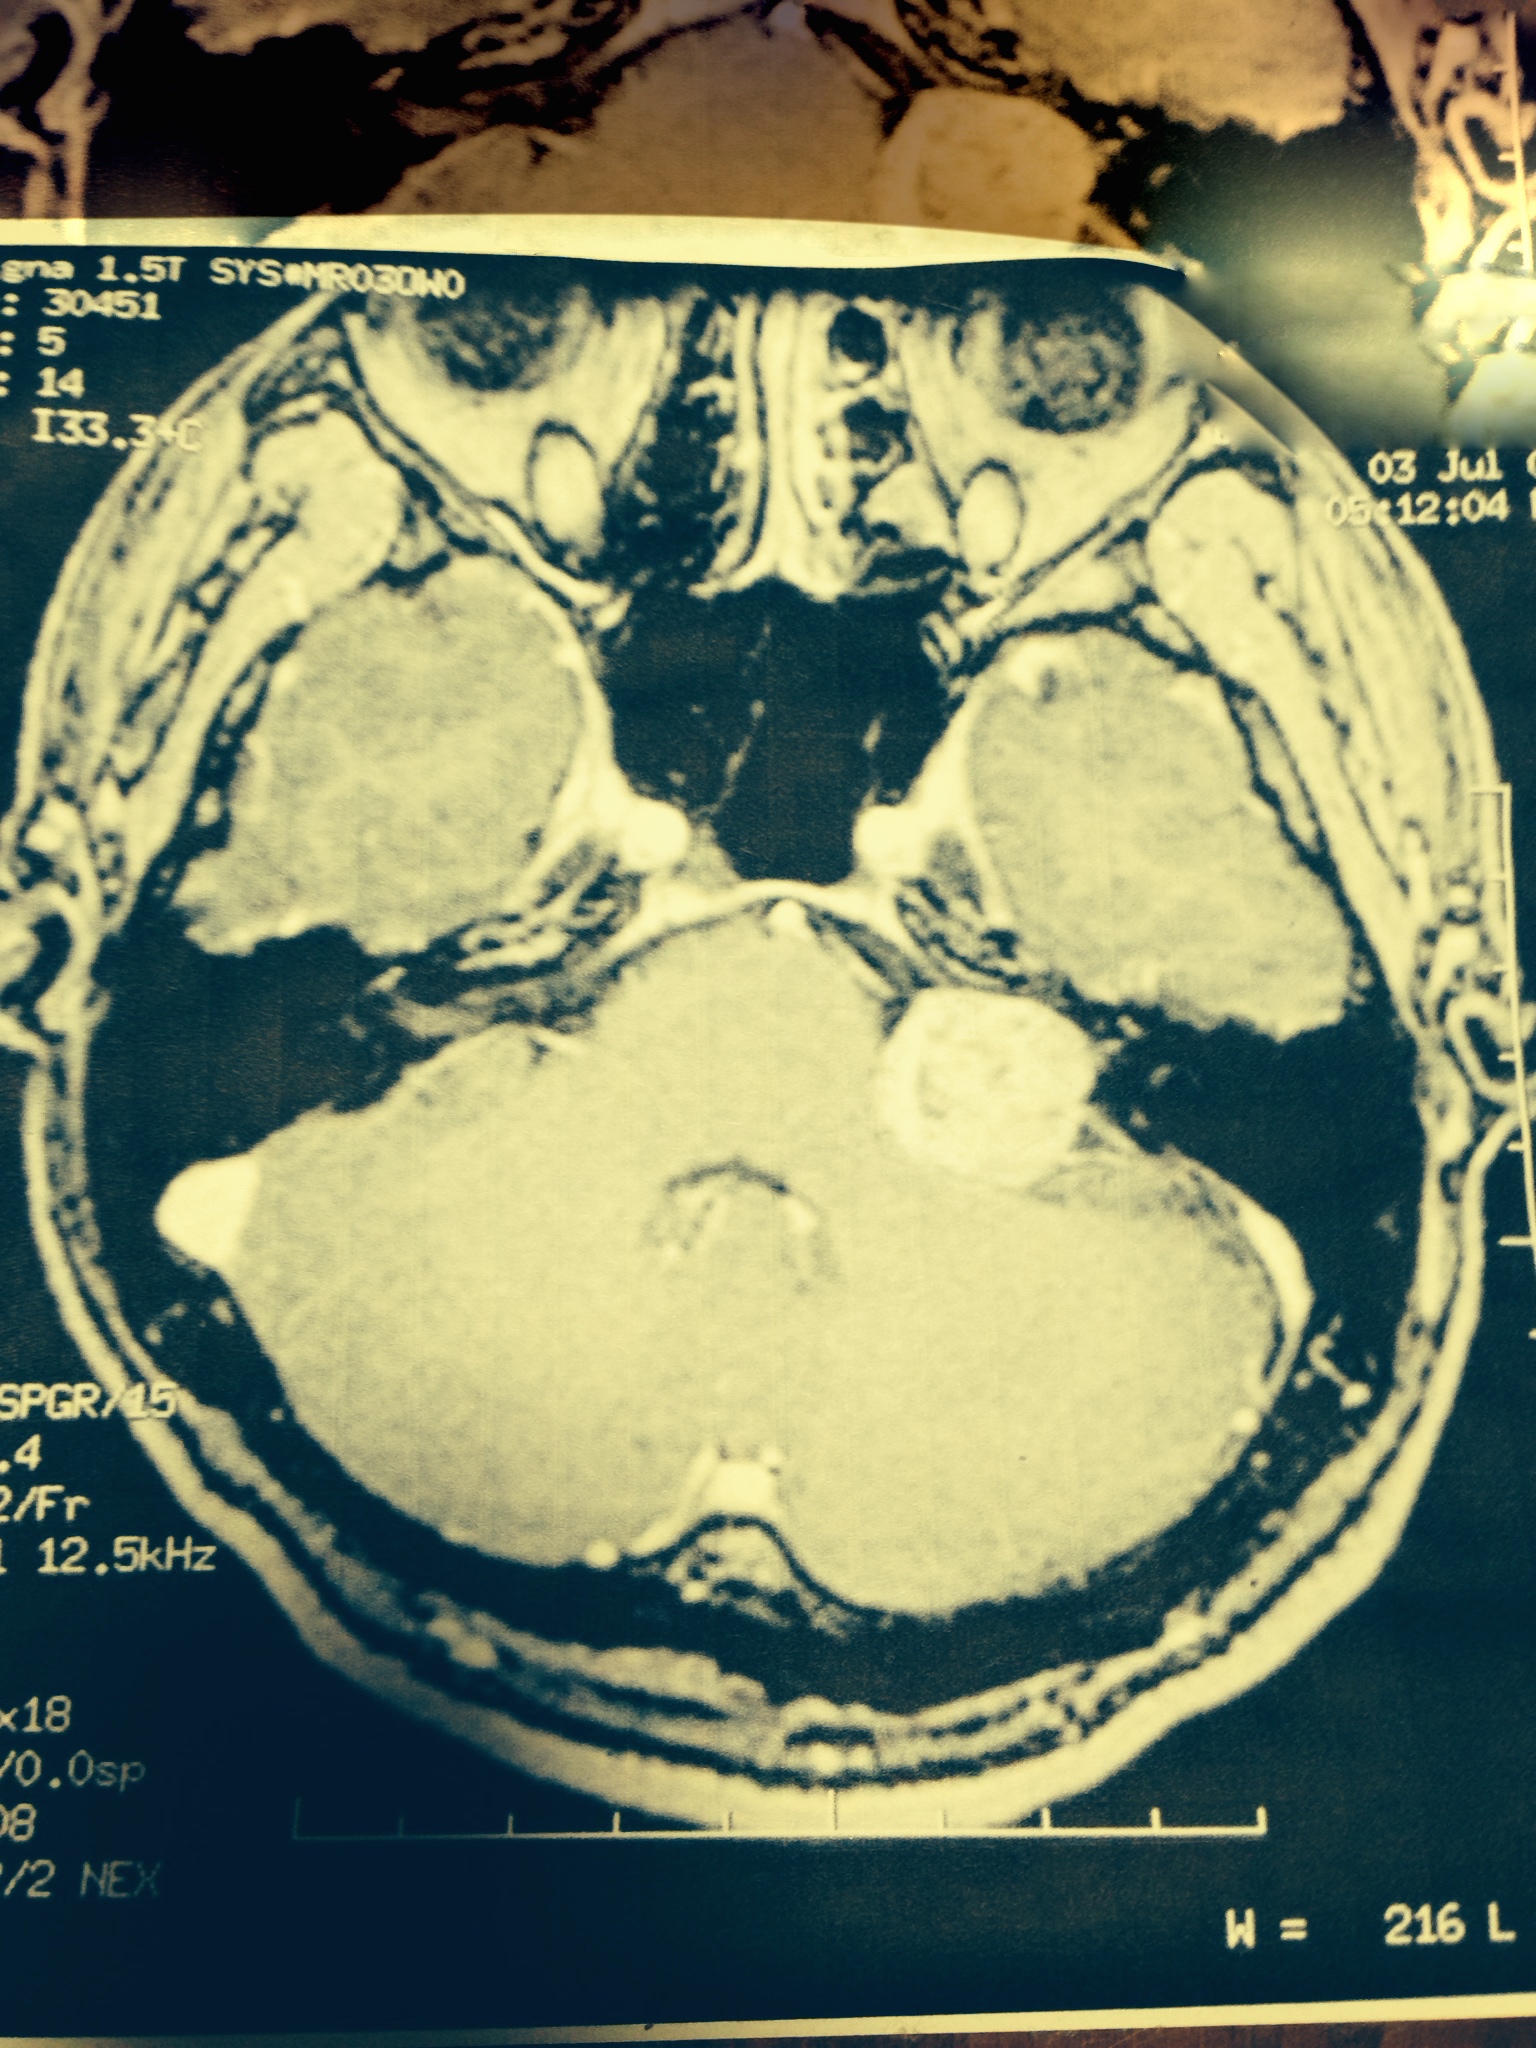

上の写真は、2001年6月3日。わたしの病気が判明したときの写真です。センター右の丸い白いものが脳腫瘍です。

この写真を見た瞬間、わたしは助からないと思いました。